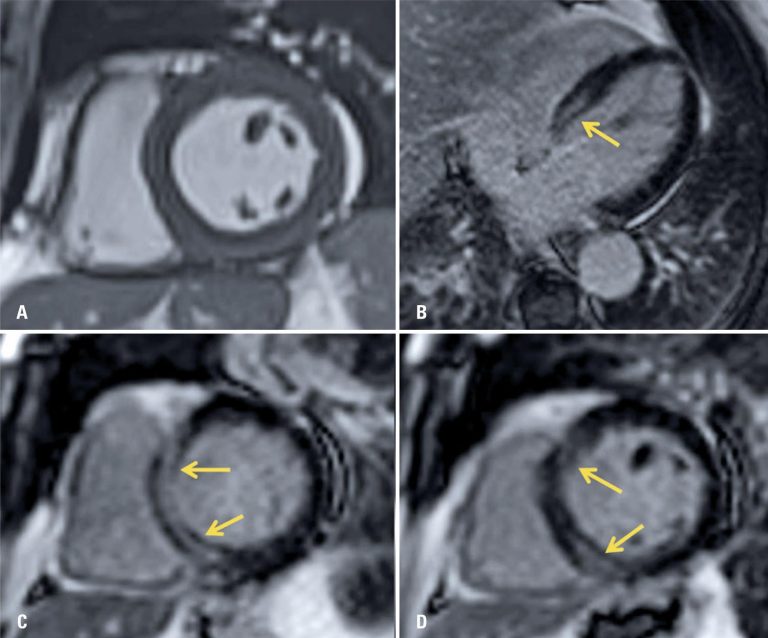

COVID-19 myocarditis: a case report

ABSTRACT A male patient with flu-like symptoms and tomography and laboratory diagnosis of severe acute respiratory syndrome. He developed acute cardiac dysfunction during admission and was submitted to a cardiac magnetic resonance imaging examination, which confirmed acute myocarditis, indicating cardiac involvement by coronavirus disease 2019. A review and discussion about coronavirus disease 2019-related cardiac manifestations are reported, focusing on the imaging findings to make diagnosis.